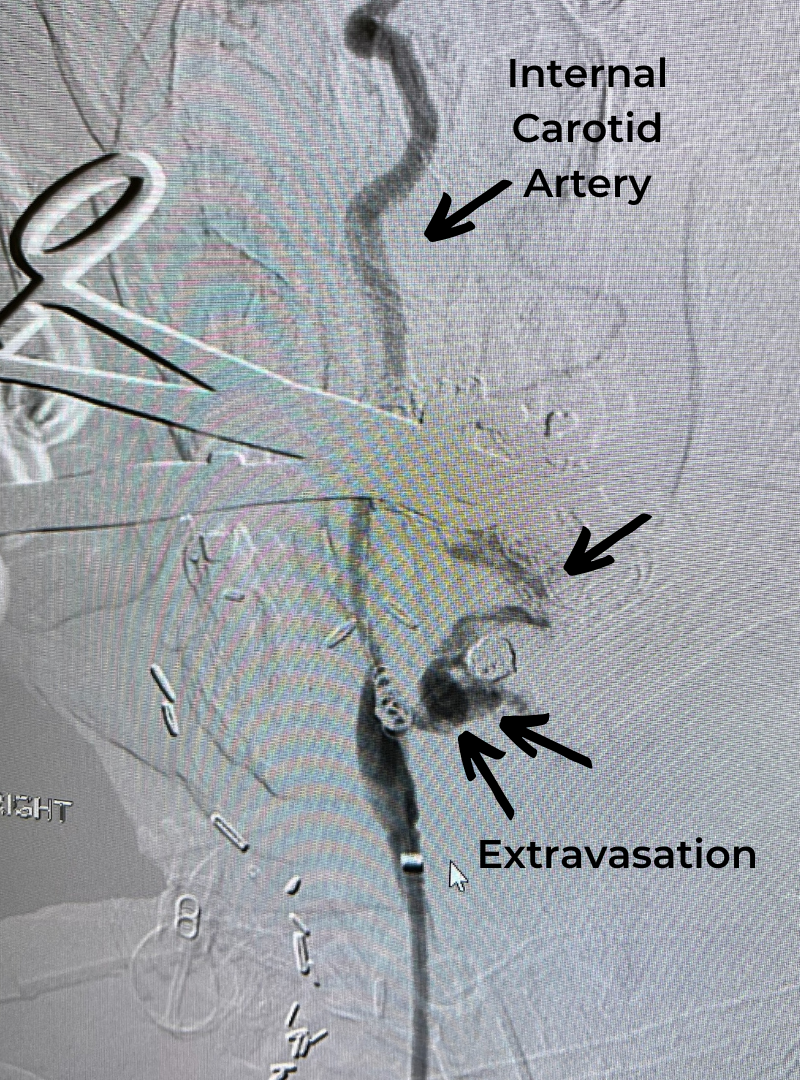

Figure 1a – Preoperative MRI demonstrating an extra-axial enhancing mass of the anterior cranial fossa.

She was started on high-dose steroid and antiseizure prophylactic medicine. Surgical intervention was offered for mass effect, symptomatic relief, neurologic preservation, and histopathologic diagnosis. Dr. Gaudin performed a bifrontal craniotomy with complete resection of neoplasm through an interhemispheric and subfrontal approach. Postoperative imaging demonstrated a gross total resection without residual tumor and resolution of mass effect (Figure 1b and 2b). Intraoperative pathology was consistent with meningioma, WHO grade 1. She recovered very well, and was discharged home on postoperative day 3. On her follow-up outpatient visit, her preoperative symptoms had fully resolved, and her olfactory sense was maintained.